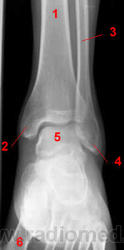

Голеностопный сустав.

1, Б/берцовая кость.

2, Медиальная лодыжка.

3, Малоберцовая кость.

4, Латеральная лодыжка.

5, Таранная кость.

6, Плюсневые кости.

2, Малоберцовая кость.

3, Таранная кость.

4, Пяточная кость.